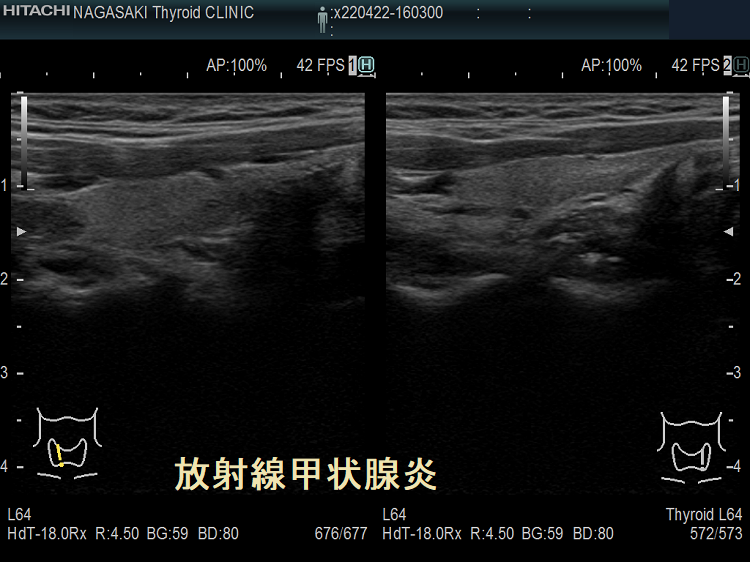

放射線甲状腺炎は、甲状腺以外の癌(頭頚部癌、頭頚部の悪性リンパ腫、頭頚部が照射野に入る肺癌・食道癌・乳癌など)に対する放射線外照射(体の外から放射線を当てる事)が原因で起こります。

放射線量により発症までの期間は異なり、数か月〜数十年後とされます。外部からの放射線量が26 Gyを超えて甲状腺組織の破壊が強いと、甲状腺は萎縮し甲状腺機能低下症に至ります。

頚部食道がん放射線治療後だが橋本病